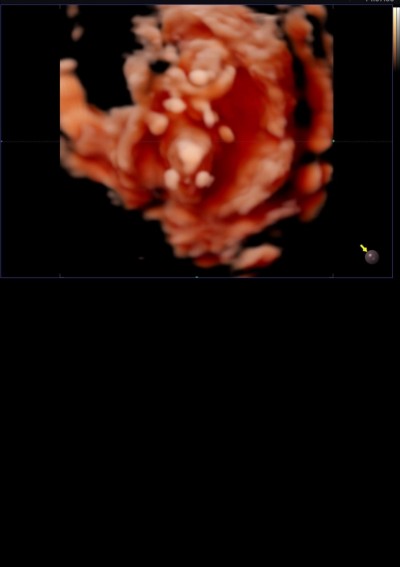

Bugun 12+2 olduk. Doktorum cinsiyet söylemek için erken söyleyemem değişebilir dedi ama ben merakımdan duramıyorum yardımcı olabilecek var mı

Erkek sanki orda minnak bir pipi var

Bende ilk önce öyle dedim ama sonra dan o göbek kordonu olabilir mi ki dedim ilk defa gördüğüm için anlamda veremiyorum

Bir pipi gördüm sanki :)